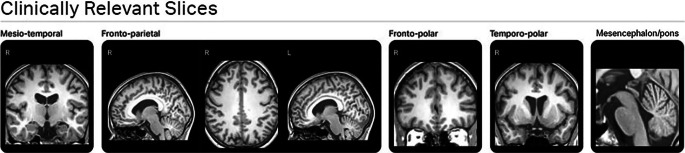

Methods: 10 healthy subjects (27.4 ± 1.71 years) were prospectively examined in a Philips Achieva 1.5T, Philips Ingenia CX 3T, Siemens MAGNETOM Aera 1.5T and Siemens MAGNETOM Vida 3T, the latter equipped with three different head coils, within one day. Brain volumetry of the whole brain, total white and grey matter, the cortical grey matter of the supratentorial lobes as well as regions important for the differentiation of neurodegenerative diseases of the dementia and movement disorder spectrum and the ventricular system was performed using the CE-certified software mdbrain by mediaire (Berlin, Germany). Both raw volumetry results and percentile allocation provided by the software were analysed.

Abstract Image